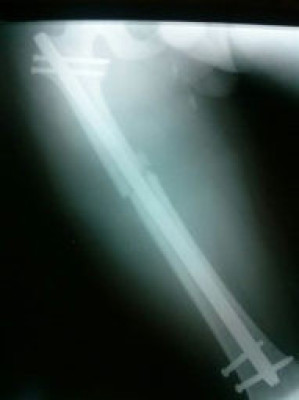

Fractura de Femur